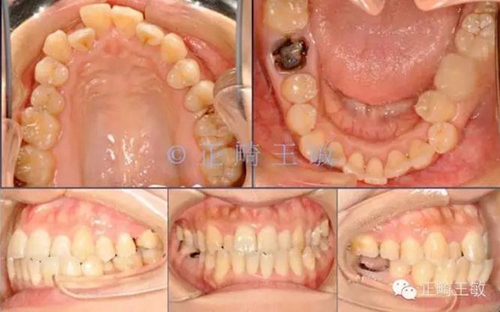

前幾天寫了篇正畸輔助種植治療的文章,簡(jiǎn)單介紹了種植間隙不足,正畸如何配合治療。幾天來(lái),好評(píng)如潮,很高興能和各位老師如此便捷的討論。今天接著寫一篇續(xù)集,如果缺牙的同時(shí),又伴有牙齒排列的問(wèn)題,該如何設(shè)計(jì)方案。

首先來(lái)看這樣一個(gè)病例:

這樣的情況看起來(lái)很復(fù)雜,缺2個(gè)牙,三類關(guān)系,擁擠,又偏又反。如何處理?

為了找到治療的目標(biāo),我先設(shè)計(jì)左側(cè)的咬合,因?yàn)檫@一側(cè)并未有大的缺牙間隙。26的缺失關(guān)閉間隙還是相對(duì)容易,不再贅述。

首先我的想法是找到最不需要移動(dòng)的牙齒,最穩(wěn)定的牙齒。發(fā)現(xiàn)尖牙的前后向關(guān)系還不錯(cuò),只是下頜還需要內(nèi)收,而左側(cè)上5已經(jīng)咬在下6的窩里,這樣的咬合關(guān)系已經(jīng)很穩(wěn)定,左側(cè)拔掉一顆下牙就足以解決下牙的擁擠和咬合的問(wèn)題。

然后來(lái)看看右側(cè)。

也同樣,尖牙很穩(wěn)定。

只是偏合,為了糾正,47的支抗不免喪失,最終會(huì)做成一個(gè)這樣的關(guān)系。

這時(shí),順理成章的種一個(gè)小一點(diǎn)的46,同樣是尖窩相對(duì),同樣的穩(wěn)定。

有了一個(gè)目標(biāo)后,矯正就很簡(jiǎn)單了,拔掉一顆牙,7個(gè)月順利讓牙齒移動(dòng)到我們想要的位置: